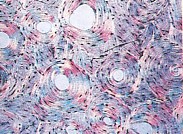

Mais grâce à la technique développée par ces chercheurs, et appelée le nanokicking, il devient possible de transformer les cellules mésenchymateuses en « amalgame » osseux en 3D. Ces greffes osseuses vivantes en 3D pourraient t d'ici quelques années réparer ou remplacer des sections d'os endommagées. Les cellules souches mésenchymateuses, naturellement produites par le corps humain dans la moelle osseuse, ont le potentiel de se différencier en toute une gamme de cellules spécialisées pour former des tissus tels que l'os, le cartilage, le ligament, le tendon et le muscle.

Le nanokicking soumet les cellules à des vibrations ultra-précises à l'échelle nanométrique alors qu'elles sont suspendues à l'intérieur de gels de collagène. Le processus de nanoculture transforme les cellules dans les gels en un « amalgame » osseux qui pourrait théoriquement être utilisé pour guérir des fractures osseuses et combler l'os là où il est lésé. L'utilisation de cellules mésenchymateuses propres aux patients (autologues) permettrait de plus d’éviter le problème du rejet.